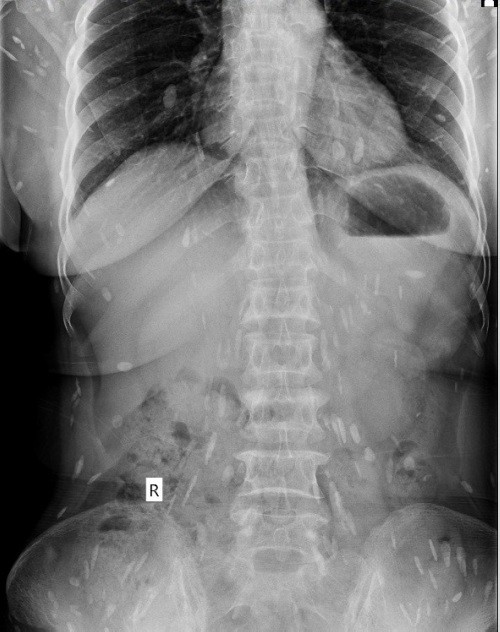

Ngày 19/3, bà Đ. được gia đình đưa đến Bệnh viện Quốc tế Vinh thăm khám. Qua thăm khám, xét nghiệm, siêu âm, chụp X-quang, các bác sĩ kết luận bệnh nhân bị mắc bệnh sán lá gan sinh sống trong cơ thể đã nhiều năm, đang sinh sôi, lan ra trong nhiều bộ phận cơ thể, báo Người Lao Động đưa tin.

Hình ảnh sán lá gan lớn khắp cơ thể bệnh nhân Đ. - Ảnh: Bệnh viện cung cấp